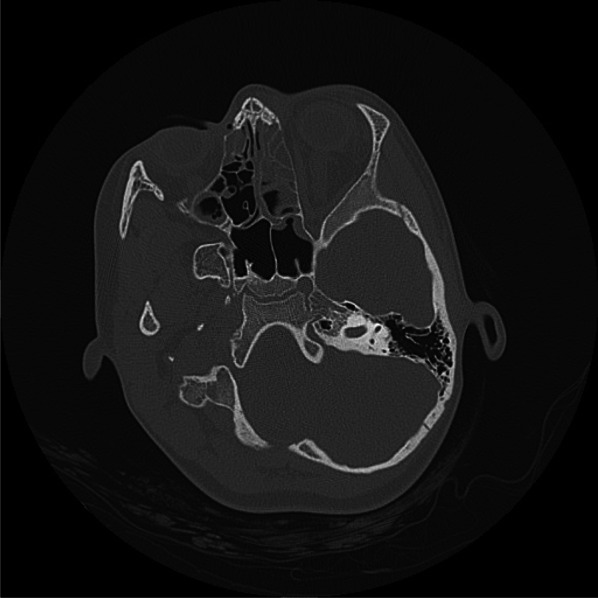

Ocular Point of Care Ultrasound (PoCUS) is emerging as a valuable utility within emergency medicine. Optic nerve sheath diameter (ONSD) has been demonstrated to correlate closely with intracranial pressure (ICP) and an elevated measurement can detect raised ICP readily, where fundoscopy may not, owing to both technical challenges and insufficient clinical skills. A previously fit and well 10-year-old girl presented to the paediatric emergency department with worsening headache, fever and lethargy. On examination, her left pupil was large, and not reactive to light. Initially, her GCS was 15 but suddenly dropped to 8/15. Her blood tests showed raised inflammatory markers. A CT head was reported as possible pansinusitis and MRI of her brain was initially reported as showing evidence of meningeal irritation only. Due to her drop in GCS PoCUS of optic nerve sheath was conducted which showed evidence of increased ICP with increased optic nerve sheath diameter of 6.8mm. This led to a reassessment of the MRI imaging by the neurosurgical team who felt there was evidence of subdural empyema. The patient was transferred to the tertiary neurosurgical centre, where an emergency evacuation of subdural empyema was carried out. Staphylococcus aureus and Streptococcus pyogenes were grown from pus samples. Early detection of raised ICP is of paramount importance in terms of being able to instigate neuroprotective measures and prevent adverse neurological outcomes. PoCUS is a readily available, non-irradiating, easily repeatable, well-tolerated and readily teachable ultrasound modality and a useful tool which should be employed in paediatric and adult emergency departments.

眼点超声(PoCUS)正在成为急诊医学中有价值的实用工具。视神经鞘直径(ONSD)已被证明与颅内压(ICP)密切相关,升高的测量可以很容易地检测到升高的ICP,而由于技术挑战和临床技能不足,眼底镜检查可能无法检测到升高的ICP。先前健康和良好的10岁女孩呈现给儿科急诊科恶化头痛,发烧和嗜睡。经检查,她的左瞳孔很大,对光无反应。最初,她的GCS为15,但突然降至8/15。她的血检显示炎症标志物升高头部CT显示可能为全鼻窦炎,脑部MRI最初仅显示脑膜刺激。由于GCS下降,视神经鞘PoCUS显示颅内压增高,视神经鞘直径增加6.8mm。这导致神经外科团队重新评估MRI成像,他们认为有硬膜下脓肿的证据。患者被转移到三级神经外科中心,在那里进行了硬膜下脓肿的紧急疏散。脓液中培养金黄色葡萄球菌和化脓性链球菌。早期发现升高的颅内压是至关重要的,能够激发神经保护措施和防止不良的神经系统后果。PoCUS是一种易于获得、无照射、易于重复、耐受性好、易于教学的超声方式,是儿科和成人急诊科应采用的有用工具。